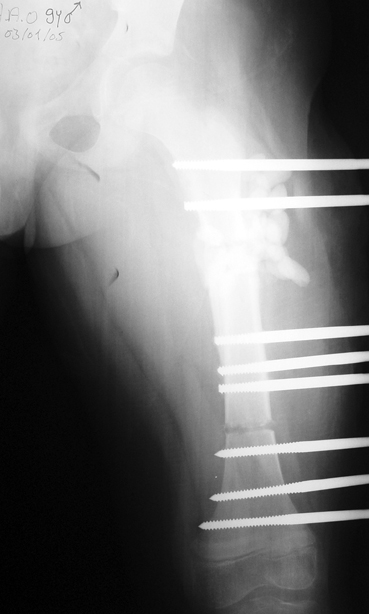

Uygun radikal debridman tüm nekrotik kemik ve yumuşak dokuların çıkartılmasını gerektirir, ve sıklıkla uzuvda instabiliteye neden olur. Kalan kemik ve yumuşak doku defektinin bir şekilde fiksasyonu ve rekonstrüksiyonu gereklidir. İlizarov’un ortaya koyduğu distraksiyon osteogenezi yöntemi, kaynamanın elde edilmesi, deformitenin düzeltilmesi, bacak boy eşitsizliğinin giderilmesi ve segmental defektlerin rekonstrükte edilmesi için başarıyla kullanılmaktadır.

Eksternal fiksatör ile geçen süre (eksternal fiksasyon indeksi), gereken distraksiyon miktarına bağlıdır ve bu süre boyunca bazı komplikasyonlarla karşılaşılabilir. Distraksiyon dönemi sona erdikten sonra, distraksiyon süresinin iki katını aşan konsolidasyon döneminde hastalar eksternal fiksatörü zorlukla tolere edebilirler. Yeterli konsolidasyon sağlanmadan eksternal fiksatör çıkartılırsa ise kırıklar, deformite ve kısalık oluşabilir. Hastanın fiksatör ile birlikte geçirdiği sürenin azaltılması ve böylece hasta konforunun ve aktivite düzeyinin arttırılması için intramedüller çivi üzerinden uzatma yöntemi uygulanmaktadır. Bu yöntemde distraksiyon dönemi sona erdiğinde kemiğin içindeki çivi statik olarak kilitlenmekte ve eksternal fiksatör çıkartılmaktadır. Stabilizasyon intramedüller çivi tarafından sağlandıktan sonra konsolidasyon dönemi gerçekleşmektedir. Bu şekilde hem eksternal fiksatörün uzun süre kalmasından hem de erken çıkartılmasından kaynaklanan komplikasyonların önüne geçilmektedir.